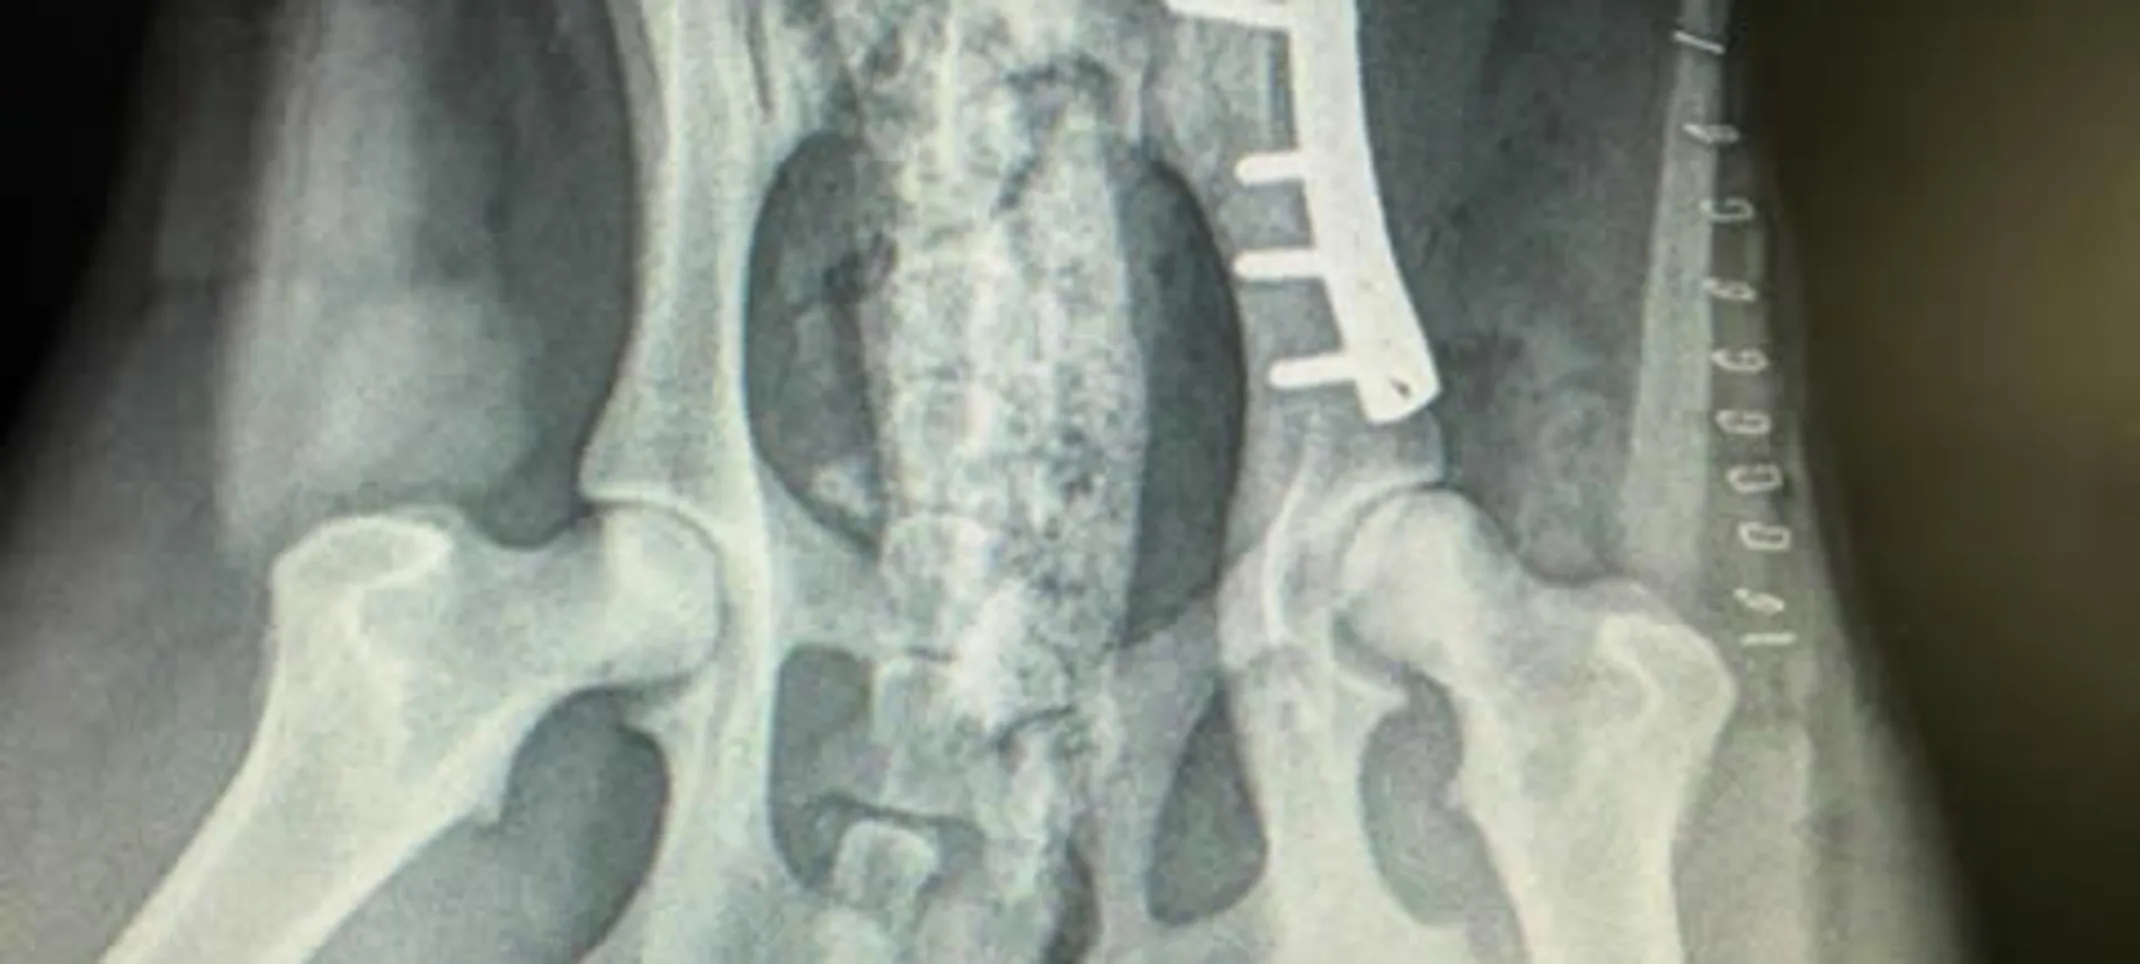

Hip fracture repair

Hip Surgery – Fracture Repair:

We use bone plates as a preferred treatment for traumatic hip fractures. This technique allows for early use affected leg and restoration of pelvic canal thus protecting against nerve damage and GI problems down the road.